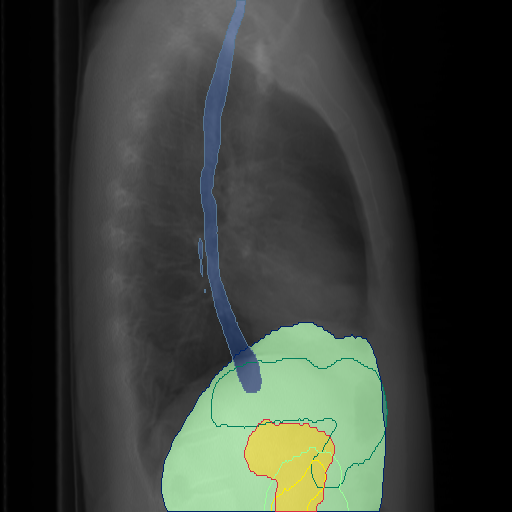

We display qualitative results in Fig. 3. The annotators tend to be content with most annotations. There are edits at the extensions of the esophagus, trachea, and aorta and corrections of the lower ribs. There is little consensus for classes in the abdominal area, such as the stomach, as seen on the right of Fig. 3 . In contrast, the annotators often align for bone classes.

We show the quantitative segmentation performance against medical expert annotations for all classes in Fig. 3 . The dashed lines represent the IAA, whereas the dotted line displays the average MAA. As the task for the human annotators was not to annotate from scratch but to correct wrong pixel-wise predictions, we can see a high MAA for most classes. In the frontal view, the most significant disagreements exist for rare bone structures such as L3 and C4, lower ribs, the mediastinal distribution, or the breast tissue. The IAA and MAA are highly similar with mIoU of respective 95% and 94%. The Hausdorff distance for MAA is slightly lower than the IAA, indicating slight differences in boundary annotations while maintaining a considerable overlap with the other annotator. In the lateral view, the concrete delineation of rib structures appears ambiguous, leading to lower MAA and IAA with a greater IAA than MAA for all metrics in this supercategory. Overall there is less agreement between the medical experts in the lateral view, leading to a better average MAA than IAA across all metrics (i.e. 85% vs 83% mIoU). While the experts propose changes to the original predictions, they are often not overlapping. In the lateral view, rib segmentations can become quite hard to interpret. While both annotators disagree with the rib segmentations, they do not always agree on how they should look. Similarly to the frontal view, tube-like structures like the esophagus are extended as they can appear fractured at times.